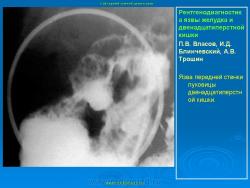

Пищеварительная система. Рентгенодиагностика язвы желудка и 12-ти перстной кишки. +

Рентгенодиагностика язвы желудка и 12-ти перстной кишки.

101.ya_.slayd45.jpg102.ya_.slayd46.jpg103.ya_.slayd16_1.jpg104.ya_.slayd17_1.jpg